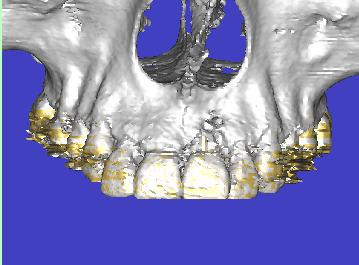

Scanner de contrôle quelques mois plus tard...

Preservation de crete - Eugenol

la procédure a permis de conserver le volume osseux disponible voir même l'augmenter, la difficulté est que le produit de comblement est radio-opaque et que sa cohésion est délicate à aprécier. peut -tu faire part de tes sensations lors du forage.